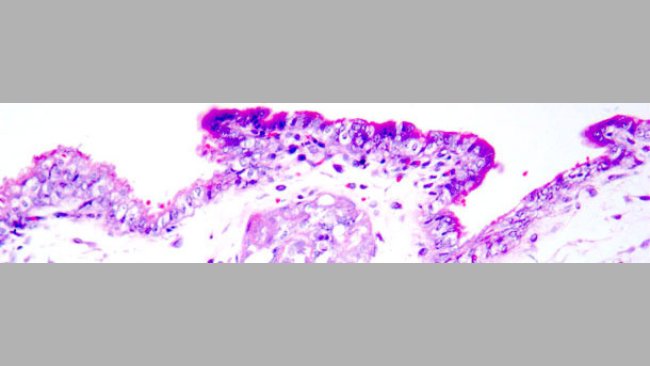

IA en nulíparas con semen contaminado con PCV2. Protección mediante vacunación de nulíparas frente a PCV2

La vacunación de las primerizas frente a PCV2 antes de la insemianción con semen infectado con PCV2 disminuyó claramente la carga y la excreción viral, hasta valores compatibles con la protección de los fetos.